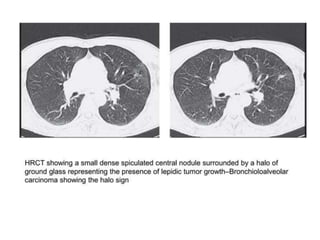

PARENCHYMAL SIGN

• Air Crescent Sign

• Monod Sign

• Halo Sign